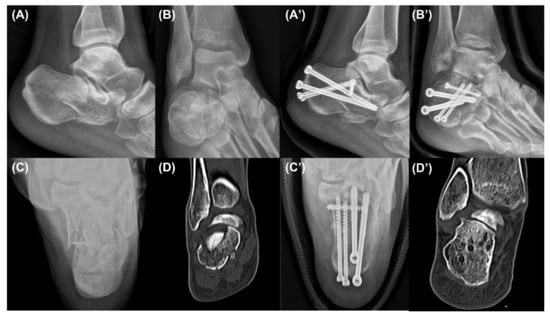

Surgical Treatment Using Sinus Tarsi Approach with Anterolateral Fragment Open-Door Technique in Sanders Type 3 and 4 Displaced Intraarticular Calcaneal Fracture

2.2. Surgical Technique